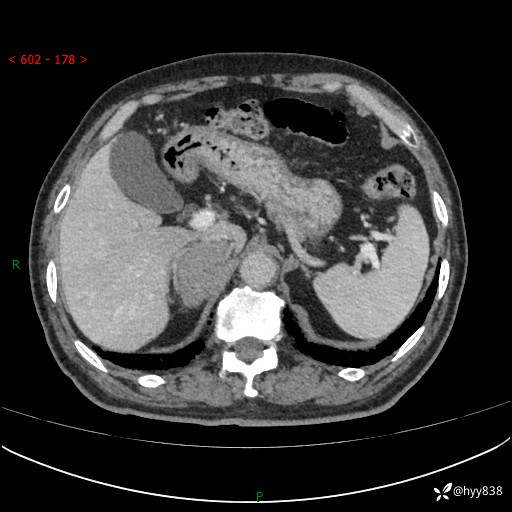

【患者信息】:76岁/男

【主诉】:检查发现右侧肾上腺占位6天

【现病史及既往史】:患者6天前体检发现右侧肾上腺占位,无腰痛,无放射痛,无尿频、尿急、尿痛及肉眼血尿,无畏寒、发热,无恶心、呕吐,今为求进一步治疗,遂来我院就诊,门诊拟“右侧肾上腺占位”收住入院。 起病以来,患者精神、饮食、睡眠可,大小便如常,体力体重无明显变化。

【检查】:肾上腺CT平扫+增强